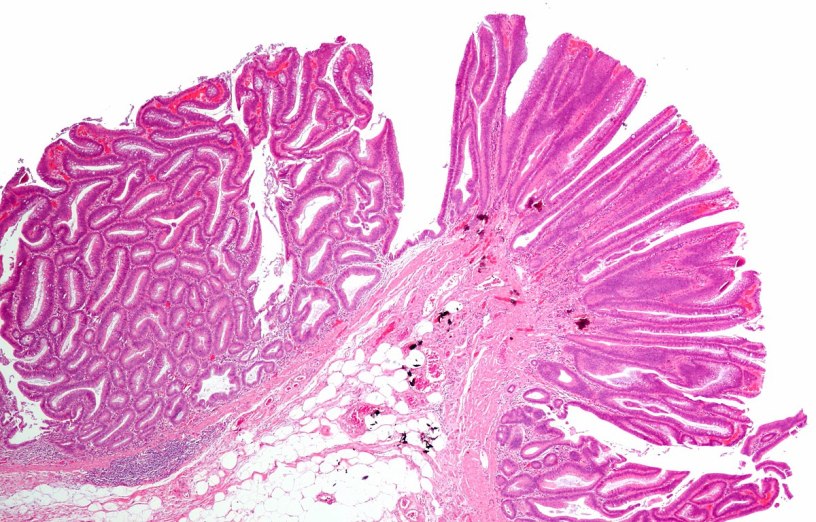

Внешний вид

Доброкачественные опухоли выглядят по-разному, бывают разной структуры и строения:

- Круглый или овальный узел, который похож по строению на цветную капусту или шляпку гриба;

- Новообразование может иметь ножку (полипы), если она связана с тканями организма;

- Кистообразные опухоли имеют вытянутую форму и наполнены жидкостью;

- Часто опухоли пронизывают ткани и поэтому их граница не определяется.

Доброкачественное образование может формироваться из любой ткани.

Кратко их можно классифицировать на следующие виды:

- Папиллома (к примеру, папиллома Шнейдера). Это новообразование считается более распространенным видом доброкачественной опухоли и легко удаляется. Обычно рецидивов не наблюдается. Выглядит новообразование как совокупность небольших стебельков или сосков, по центру которых находится кровеносный сосуд. Заболевание возникает при воздействии на организм человека вируса папилломы. При прикосновении вызывает дискомфорт и болезненные ощущения. Сюда же относят и бородавки. Все они относительно безопасны. Исключения составляют лишь образования, которые кровоточат или приносят боль, а также растущие (опухающие) или меняющие цвет;

- Аденома. Для нее характерно повторять форму органа, на котором она формируется. Это образование состоит из железистого эпителия и редко переходит в злокачественное. Хотя аденома не представляет особой опасности, но может значительно ухудшить качество жизни. Чаще она встречается у мужчин после 45.Симптомы заболевания – болезненное и учащенное мочеиспускание, снижение сексуальной активности, бесплодие;

- Эпителиома. Самый распространенный вид доброкачественной опухоли, формируется из плоскоклеточного эпителия тела человека;